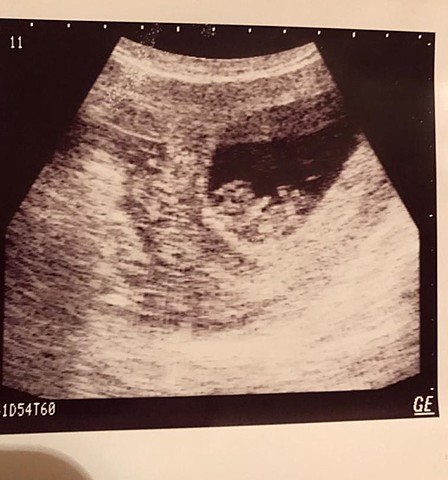

• Etapa prenatal (periodo zigoto)

Etapa prenatal (periodo zigoto)

El ovulo y el esperma se juntan para formar una nueva vida.

Se formo alrededor de un contexto que mi madre se sorprendió mucho por que no podía tener hijos por una complicación con su primer embarazo, pero en ese momento mis padres estaban en un proceso de separación. A pesar de eso mi madre al enterarse empezó a informarse sobre los cuidados necesarios para nacer sanamente para ya no tener complicaciones, ya que viviendo sola tenia miedo de que tuviera problemas al nacer.

• 2da Etapa prenatal (Periodo embrionario)

2da Etapa prenatal (Periodo embrionario)

El embarazo se formo con naturalidad, no hubo complicaciones al respecto, me ponía música, me cantaba, me leía cuentos y se alimentaba sanamente y poco a poco fui creciendo rápidamente. Para ese entonces mi madre decide mudarse de nuevo a otro estado para que mi abuela la cuidara, ya que totalmente hubo una fractura en la relación de mis padres y mi madre prefirió irse como medida de solución, pero emocionalmente estaba feliz y triste a la vez durante el embarazo.

• 3ra Etapa prenatal (Periodo fetal)

3ra Etapa prenatal (Periodo fetal)

Se culmina el embrión y nace.Tuve que nacer por cesaría por que mi bolsa se quedaba sin agua, nací en perfectas condiciones, mi madre tenia todo preparado materialmente, mi familia materna me recibió con mucho amor y mi madre estaba feliz. Cabe recalcar que mi padre no estuvo en mi nacimiento por la separación.